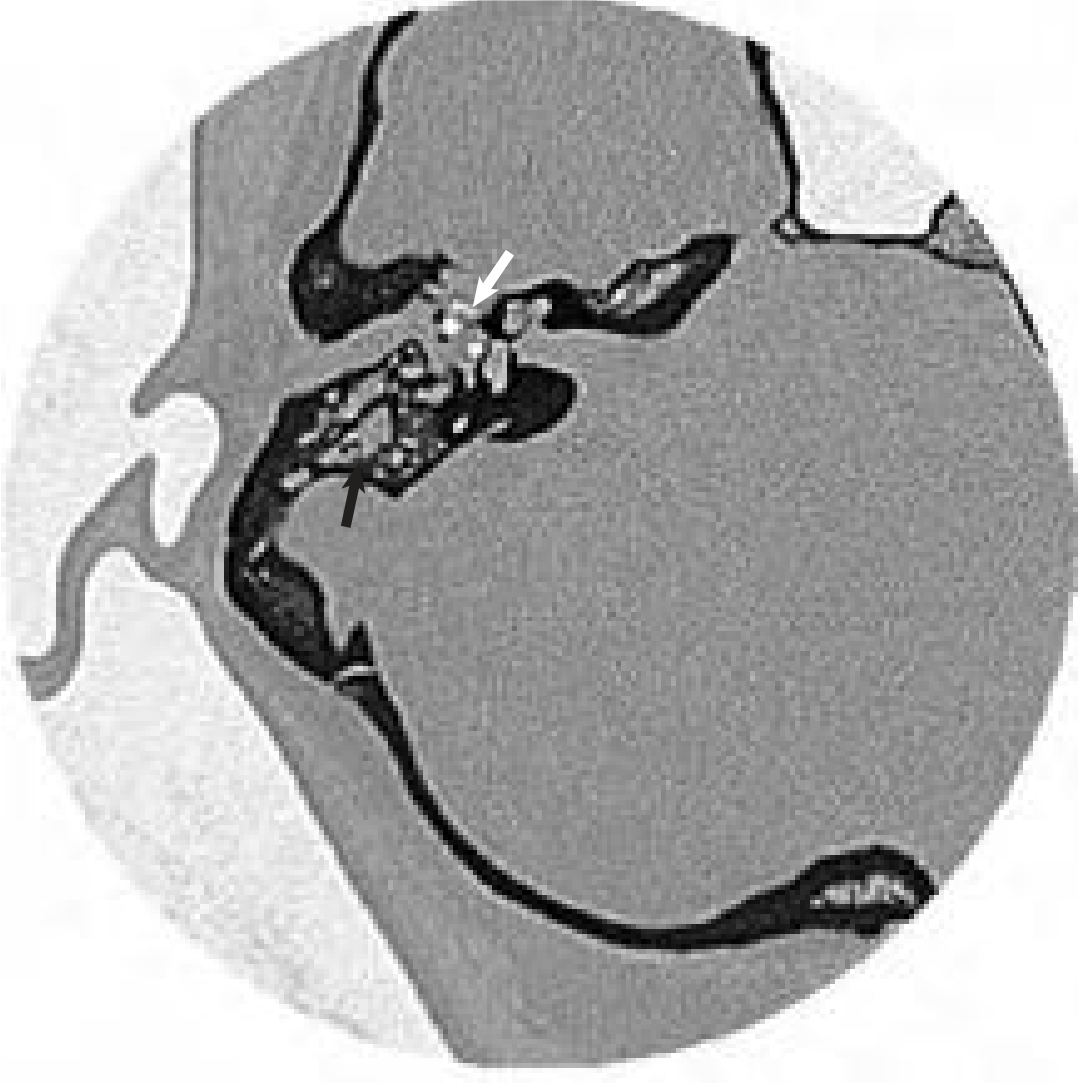

Axial temporal bone CT — opacification of the middle ear (white arrow) and mastoid (black arrow)

Fig. 141.3 CT scan: opacification of middle ear (white arrow) and mastoid (black arrow). — Cummings Otolaryngology